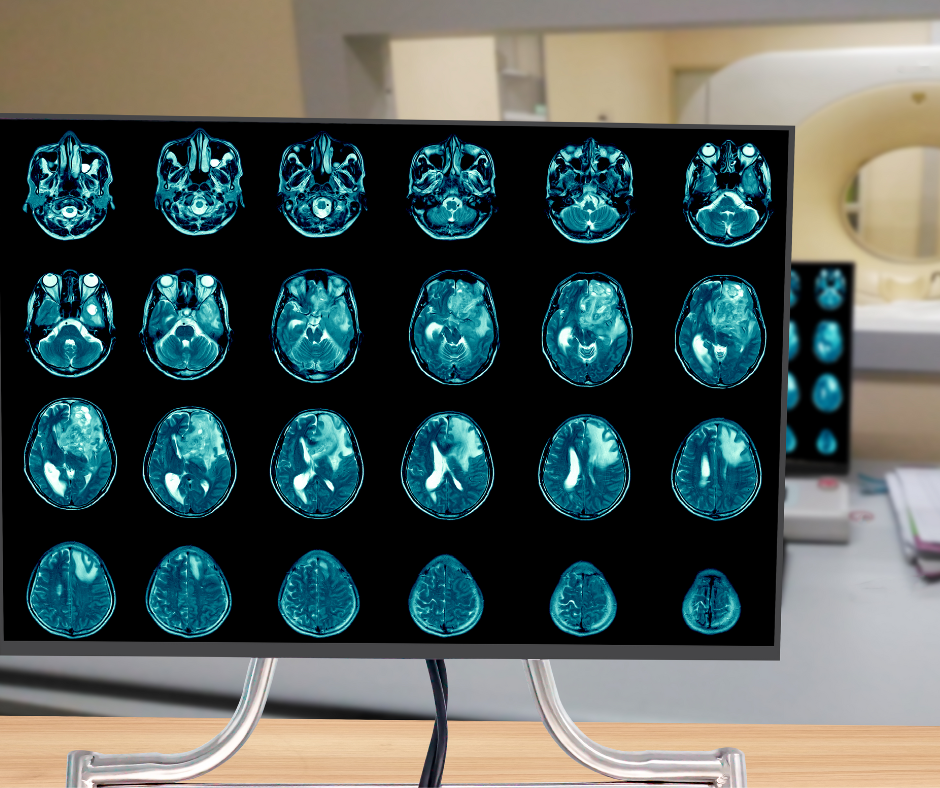

The advisory emphasizes that the computer-aided triage and notification (CADt) devices, many of which incorporate artificial intelligence (AI) or machine learning technology, are intended to aid radiologists in prioritizing the assessment of brain imaging that may reveal signs of large vessel occlusion (LVO).

The new artificial intelligence (AI) algorithm reportedly flags suspected cases of brain aneurysm and facilitates multidisciplinary care.